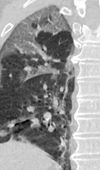

Case Report

CT Features of COVID-19: A Case Report

We describe here the Chest CT imaging features of a 68-year-old man presenting with fever (37.5 ℃), malaise, dyspnea and persistent dry cough for 7 ... Read more